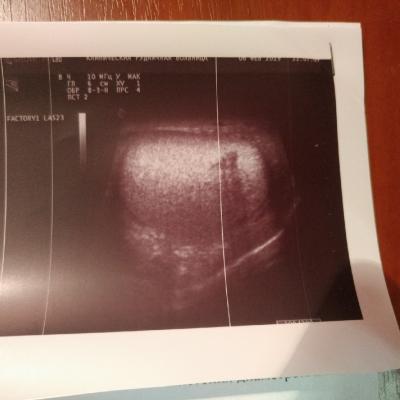

Год назад мне сделали операцию метод Мармара при варикоцеле. До сегодняшнего дня размер моего левого яичка не уменьшился в норму. Болей нет. Уплотнения есть, вены расширены, но, как мне сказали, незначительно. Всё указано в УЗИ.

Здравствуйте! Судя по результатам УЗИ в разные сроки.отмечается всё же динамика - уменьшение размеров яичка и придатка слева. Посоветуйтесь с Вашим урологом по поводу приёма препарата Детралекс для улучшения микроциркуляции. Удачи!